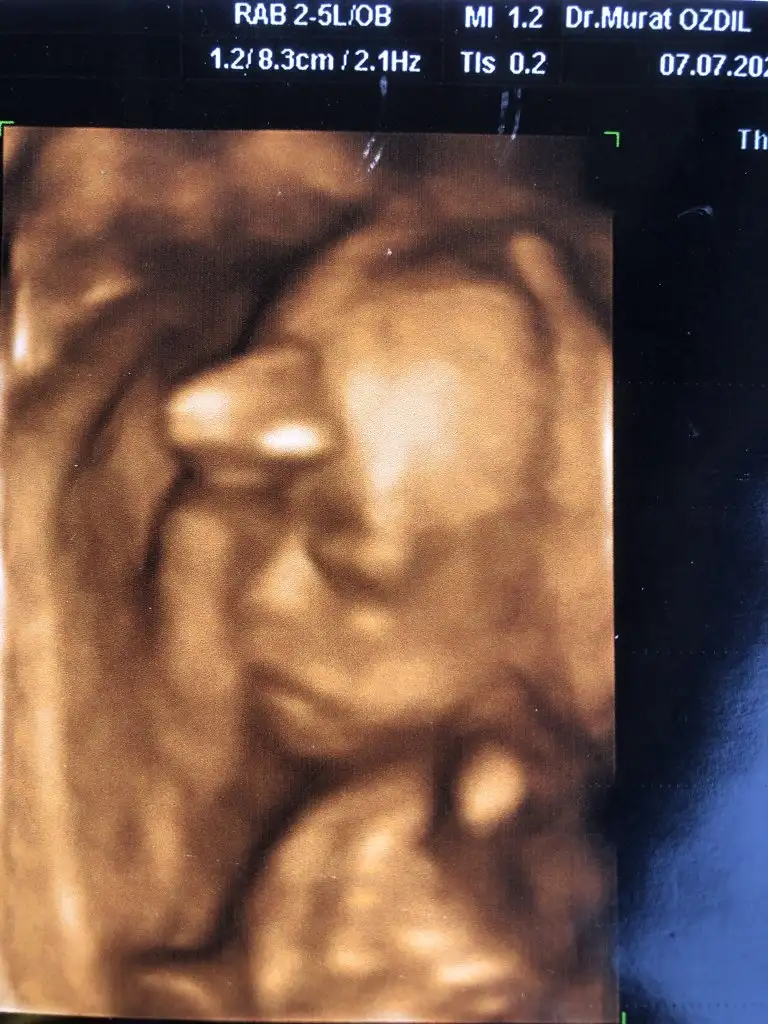

Detaylı ultrasona geldik çok heyecanlandım 😃 inşallah güzel geçer 🙏 4 haftadır görmüyorduk bakalım yüzü falan nasıl 🙈🙈 çikolata yemeyi unuttum ama 😟

Var mı minnoşun güzel bir pozu ❤️

Kızlar biz Van’da görev yapıyoruz bizim bulunduğumuz ilçe Vana 2 saat falandı. O ilçede kadın doğum yok diye biz merkeze gidiyorduk. Tayin olarak Eskişehir taraflarını düşünüyoruz. Yada neresi açılırsa artık. Puanımıza da bağlı tabi. Ama bizim bulunduğumuz ilçe gerçekten mahrumiyet bölgesi çok sıkıldık bunaldık orda. Çocuk orda hasta olsa bişey olsa doktor yok teçhizat yok. Açıkçası tayinimizin nereye çıkacağı taşınmadır vs en büyük derdimken şimdi hiç umrumda değil. Ben zaten Aydınlı olduğum için Aydın, İzmir tarafında da iyi bir doktor bulsam bana yeter, zaten doğum iznim olacak. Ama anladığım kadarıyla cesaretli, bilgili bir doktor bulmam lazım. Kendi gittiğim doktorumdan doktor tavsiyesi de alacağım. Ben tabi anlık baya etkilenip moralimi bozdum. Çünkü adam resmen enerjimizi sömürdü. Ağlamak üzereydim hala diyor ki tabi etkilenme bunlardan yanlış anlama diyor utanmadan lanet olası doktor. Neyse ben yine de moralimi bozmuyorum. Çünkü ordan çıkıp bir sonraki gittiğimiz doktor da olumsuz konuşmadı. Birde fotoğrafını da atayım 💜💜